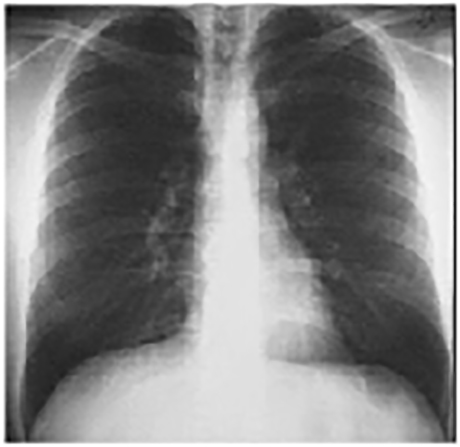

PA

These chest X rays are normal. The PA view demonstrates no abnormalities of the bone structures, lung fields, or cardiac silhouette. The right and left heart borders are normal as are the great vessels superior to the cardiac silhouette. Note the cardiothoracic ratio is also normal, that is, it is less than 50%. The lateral view is normal, with no evidence of chamber enlargement including the normal anterior shadow of the right ventricle and posteroinferior shadow of the left ventricle.